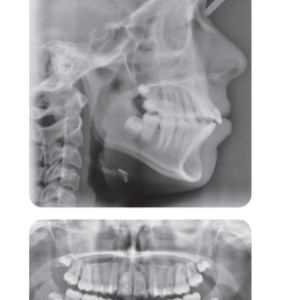

Bệnh nhân nữ 16 tuổi có sai khớp cắn hạng III trên nền xương hạng II nhẹ với tăng kích thước dọc phức tạp bởi chen chúc nhẹ và hô 2 hàm (Hình 1, Hình 2)